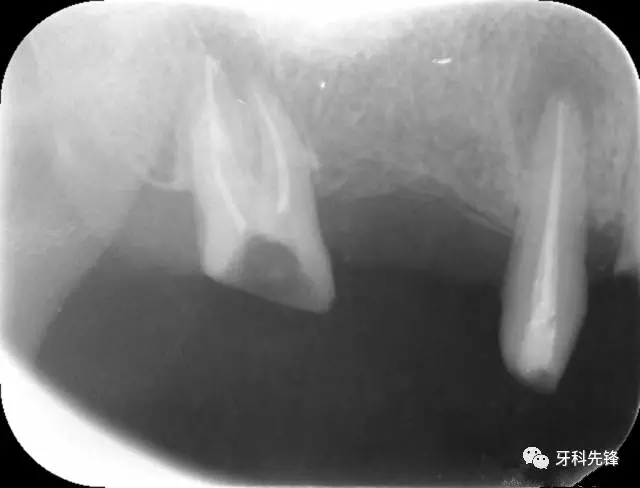

圖8治療術(shù)后X光片

640.webp (10).jpg

640.webp (11).jpg

640.webp (12).jpg

圖18 14  15   三個月后X光片(根尖陰影減?。?/p>

640.webp (22).jpg